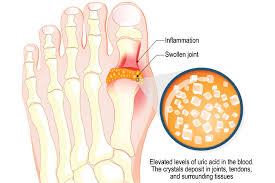

통풍은 요산이 과다로 생성되거나 요산의 배출에 장애가 발생할 경우 통풍 증상이 나타나게 됩니다.

요산이란 우리가 먹는 음식이 소화되어 최종적으로 대사하고 난 후 나오는 물질입니다. 보통 혈액 내에 녹아 있다가 소변으로 배출됩니다. 통풍 환자는 혈액 내 요산이 지나치게 많습니다. 이처럼 과다 축적된 요산은 결정체로 변하고, 이 요산 결정체가 관절 내에 침착하여 염증을 유발합니다.

통풍은 요산을 생성하는 퓨린이 다량 함유된 음식을 장기간 섭취하거나 술과 기름진 음식을 많이 섭취하여 몸 안에 요산이 축적될 경우 서구화된 식습관과 운동부족 스트레스 과다 체중 증가 등으로 인해 요산이 과다 생성되며 이들이 체외로 배출되지 못하고 관절과 힘줄 등에 쌓여 극심한 통증을 유발하게 됩니다.